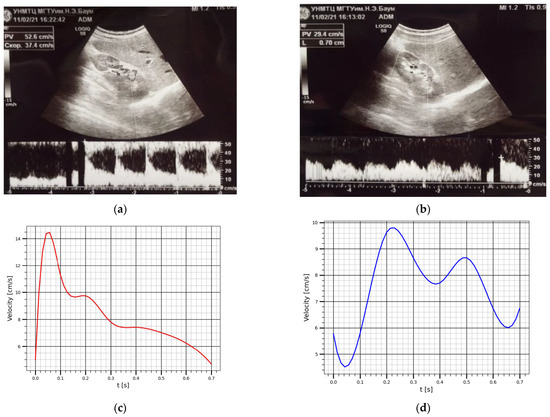

3.2. Verification with Doppler Ultrasound